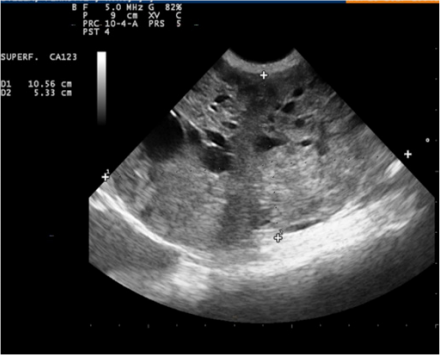

Macroscopic and Physical Examination of the dog also revealed slight depression, 4.1 kg in weight, body condition score (bcs) 3/5, normal mucosae, normal lymph nodes, temperature 38.2, 90 beats per minute, 66 breaths per minute, major organ functions in the standard. At abdominal palpation, a firm ovoid mass was detected and ultrasonography (US), thoracic radiology and haemato biochemistry were then performed and were in the standards for a 5-year-old dog (data not provided). US examination showed an ovarian mass of about 10 cm in longitudinal diameter and cm 5.5 in transverse (Figure 1). The mass had distinct margins and parenchyma of the medulla was rich in an echogenic, ovoid, cystic areas, parenchyma of cortex was dis-homogeneous, varying from hyperechogenic to hypoechogenic. From the US exam, a suspicious diagnosis of ovarian neoplasia was made and thus prompt surgical intervention was planned. Ovary-hysterectomy showed a 10cm in medium size, irregularly round, red brownish in colour, firm in consistence mass (Figure 2). On the cut surface, in the cortical region, there were several haemorrhagic, necrotic areas, with the presence, in the medullary region, of different cystic structures with serous content, varying in size from a few millimetres to 1.5 cm in diameter.

Figure 1: Ultrasonography showing an ovarian mass with distinct margins and parenchyma of the medulla rich in an echogenic, ovoid, cystic areas.